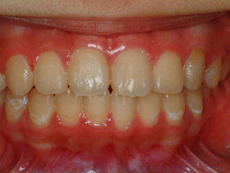

叢生(別名:乱ぐい歯、八重歯) 矯正治療後

叢生(乱ぐい歯) 矯正治療後 正面

矯正治療後 正面